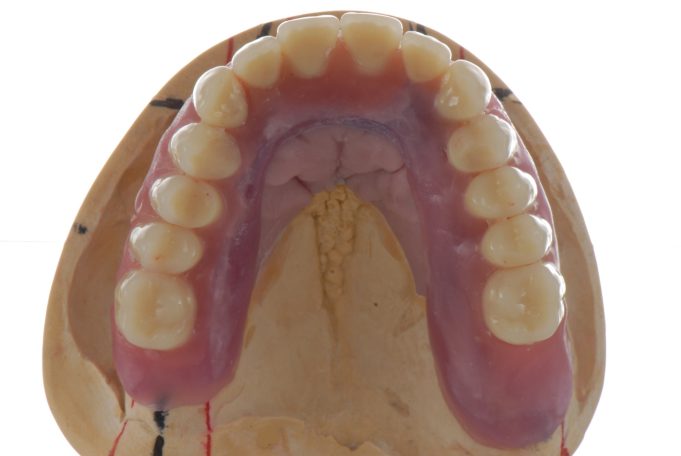

Teleskopierende Oberkieferbrücke mit Vorher- und Nachher-Situation des Patienten.

Teleskopierende Oberkieferbrücke. Wie die eigenen Zähne, aber einfach zu reinigen.